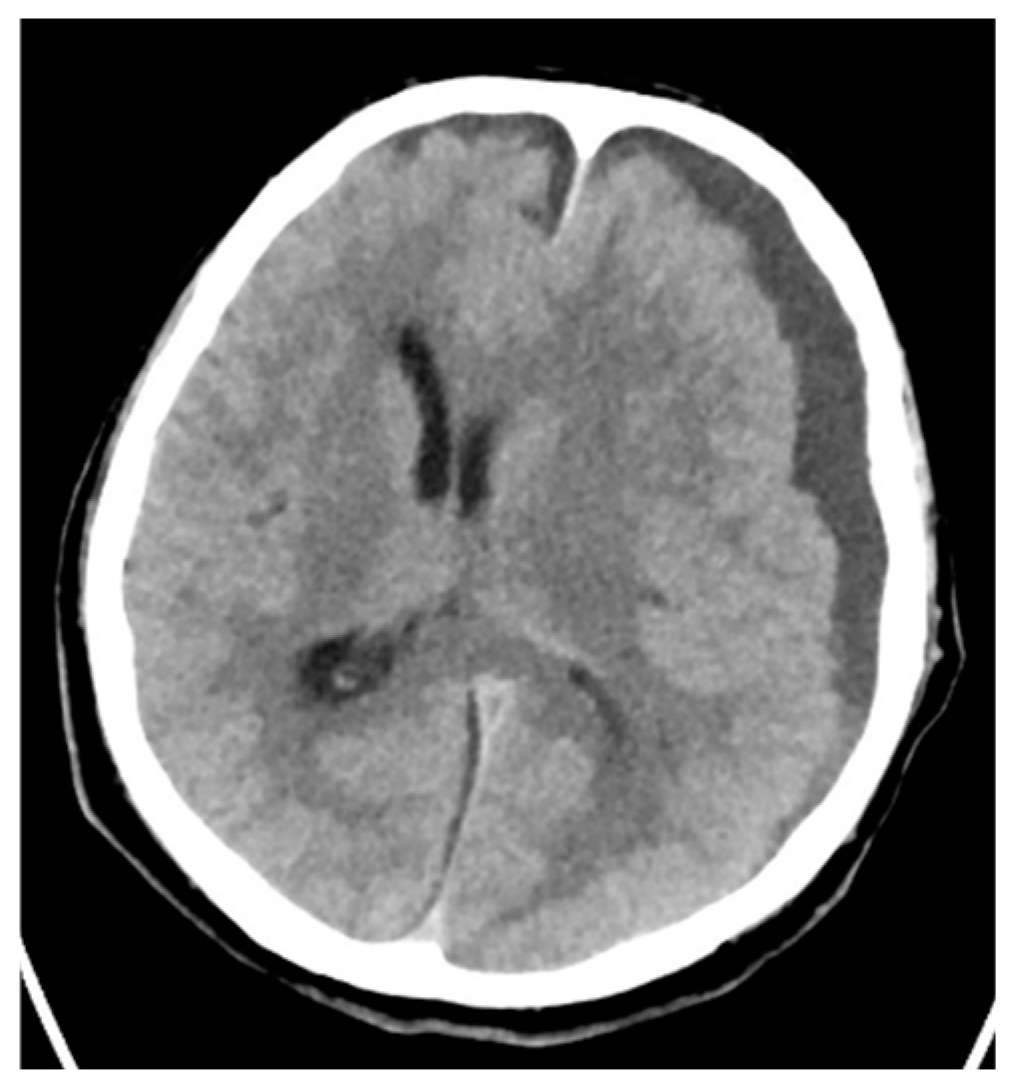

| 4 | 67/M | Otitis media Cerebral abscess | Hypertension Gastroesophageal reflux disease | no | 23 | 13 | yes | 27 days | Discharge |